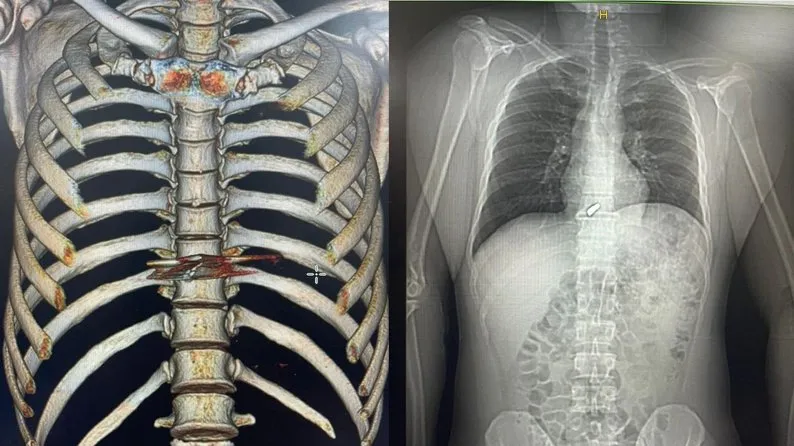

У него было четыре шаровых ранения

Он получил четыре шаровых ранения, одно из них в шею. Позже оказалось, что пуля с шеи попала в сердце. Но "Туз" преодолел тяжелый путь. Он признался, что смог пережить этот путь с помощью мыслей о дочерях.

"Никто не мог даже представить себе, что ранение шеи может привести к такому расположению пули. В правом предсердии. Сложное место. Оно находилось именно в полости сердца", – рассказал военный врач Ярослав Телушко.

Сам Туз сказал, даже не подозревал, что пуля добралась до сердца.

Я не чувствовал, что у меня пуля в сердце, честно. Врач также говорил, что ты не похож на человека с пулей в сердце. Потом сделали операцию, действительно вытащили шар. Ничего я не чувствовал, у меня все болело, в принципе, но сердце не болело,

– рассказал защитник.

Также у бойца оказался сложный перелом костей обеих предплечий и ранения ноги. Ранение он получил в результате пулеметных обстрелов. Также воин сам покончил с собой турникет.